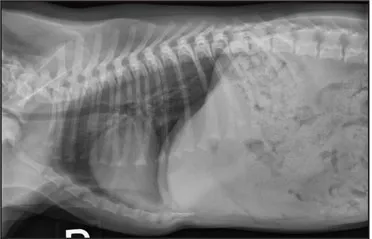

CASE 1.1 A 7-year-old neutered male Labrador Retriever who was hit by a car. You obtain these thoracic radiographs: Figs. 1.1a, b, left and right lateral projections, respectively; Figs. 1.1c, d, ventrodorsal and dorsoventral projections, respectively.

1.1b